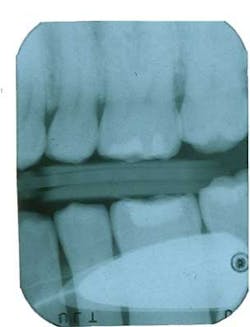

Here is our latest in a series of images for you to help identify the problem. Respond correctly for a chance to win a $25 gift card. What did the operator do wrong to achieve this image? Click here to answer.Be sure to look for the cause of the problem and Chris’s recommendation in our next article!Contact us